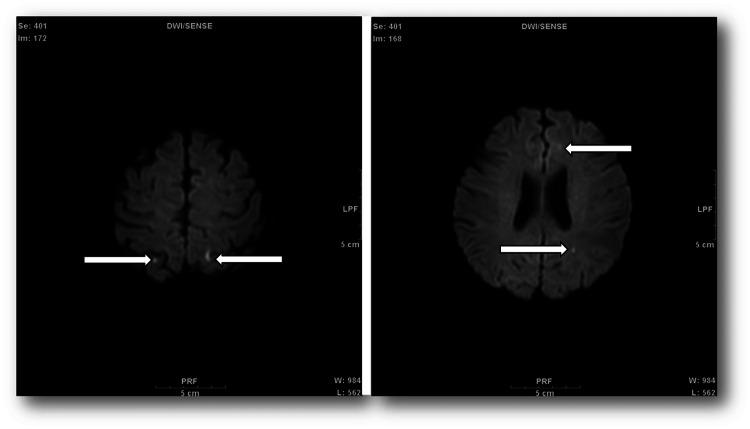

Secondary headache is a symptom of an underlying disease. Infective endocarditis (IE) is a serious infection of the heart tissue. Herein, we present a rare case of IE, with a secondary headache. The patient presented with persistent headache, fever of 39°C, myalgia, and painful erythema of the plantar surface of the foot. The headache progressively worsened over a few weeks. She was diagnosed with secondary headache, and sepsis was suspected. Blood culture revealed the presence of leading to a diagnosis of IE. Postoperatively, the patient recuperated without any complications. Headaches can be secondary to other conditions. Therefore, comprehensive assessment and accurate diagnosis are essential. Dentists must be aware that headache is a concomitant symptom of IE.

继发性头痛是潜在疾病的一种症状。感染性心内膜炎(IE)是心脏组织的一种严重感染。在此,我们报告一例罕见的伴有继发性头痛的感染性心内膜炎病例。患者表现为持续性头痛、39°C发热、肌痛以及足底疼痛性红斑。头痛在数周内逐渐加重。她被诊断为继发性头痛,并怀疑有败血症。血培养显示存在[此处原文缺失相关内容],从而确诊为感染性心内膜炎。术后,患者康复且无任何并发症。头痛可能继发于其他病症。因此,全面评估和准确诊断至关重要。牙医必须意识到头痛是感染性心内膜炎的伴随症状。